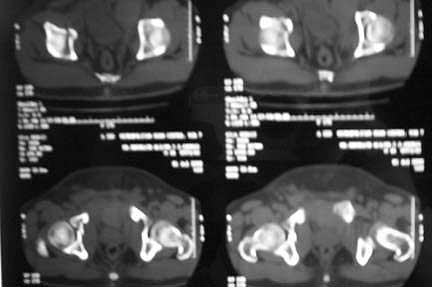

Middle aged male who was injured when a log of wood fell on him ina saw mill. Haemodynamically patient stable. No visceral injuries detected. The following musculoskeletal injuries detected: 1) Closed fracture femur. 2) Pubic symphysis disruption. 3) Right inf pubic rami fracture. 4) Right acetabular fracture. Head of femur located. 5) Right Sacroiliac joint anterior opening.

Your plan sounds fine. The acetabular fracture looks like a high ramus fracture that happens to enter the acetabulum. The CT scan is blurry, and you haven't provided any oblique views of the acetabulum - but my guess is that the 'tab is concentric.

Thank you very much for your various contributions on this case. At about 36 hours after presentation this case was taken up for surgery and by this time it was obvious that there were no visceral catastrophies that were hidden. Patient who was a chronic smoker started running a low grade fever and a cough with yellowish sputum at this time. Antibiotic cover was given adequately. The lab values just before the surgery showed a rise in CPK to the tune of about 1200 units and all other haematological and biochemical parameters were well within normal limits. Closed nailing of femur and external fixation of pelvis with closed reduction of pubic symphysis were done to get an acceptable position. Immediate post op time the thigh was swollen but not tense. Lab values soon showed another 1000 units rise in CPK and urine was quite dark. Our nephrology colleague started to alkalinise the sytem by giving sodabicarb IV. In a couple of hours the thigh became quite tense and an emergency fasciotomy was carried out in the ICU. The next 12 hours showed an increase in CPK by about 5000 units thus taking it well above 7000 units. Having got an established Rhabdomyolysis, Diuretics were started along with alkalinising. Nephrology colleague warned us on the fluid which has gone to third space coming back as the Rhabdomyolysis settles down. Sure enough as the CPK started to come down pulmonary function started to deteriorate. Patient had to be put on ventillator about 48 hours after surgery was over. To day his lungs are better and weaning process has started.